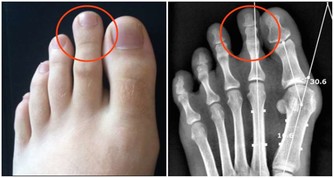

腳部拉筋,簡單一招,最有效!

拉腳部的筋不能用常規的拉筋的方法,最好的方法是雙腳底底面相對互相對拍。